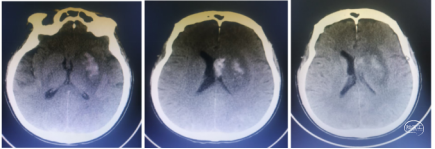

入院后急查CT未见出血和低密度改变。核磁DWI示:左侧大脑半球梗塞,左侧大脑中动脉和内囊区域受累。MRA示:左侧颈内动脉未显影,考虑闭塞。

复查CT:左侧大脑中动脉M3、M4段区域浅淡低密度影,脑中线略偏移。无出血,

给予阿司匹林100mg+氯吡格雷75mg+阿托伐他汀20mg双联抗血小板聚集治疗。